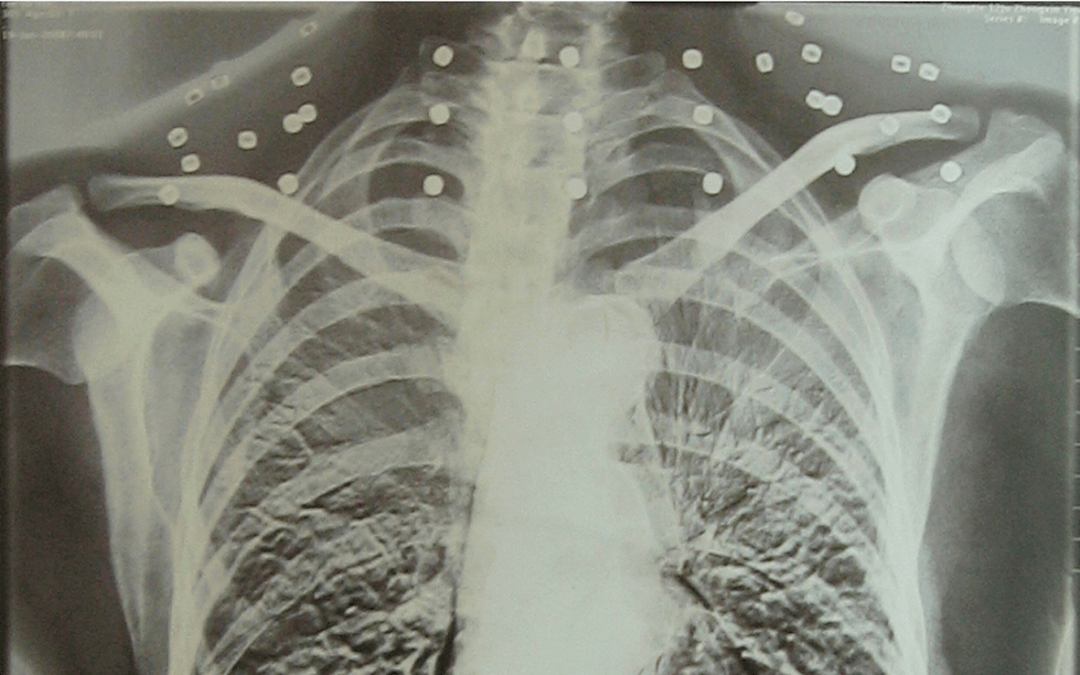

这张照片

是今年82岁的吴以先老人

拍摄的一张CT照

吴以先的颈部和腹部

共分布着33枚弹片

皇冠登一登二登三区别他体内的弹片都没有取出

身体留有弹片的位置就有痛感

在皇冠登一登二登三区别他看来

这是皇冠登一登二登三区别他与战友并肩作战的见证

是皇冠登一登二登三区别他的勋章

与吴以先身上那33枚弹片

33枚“军功章”

是一名军人的光荣